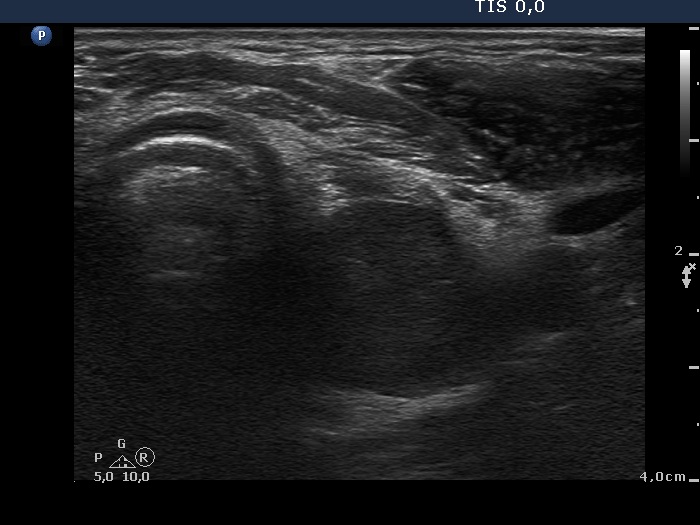

Ultrasonography. The thyroid lobes were composed of hypoechoic discrete areas. The vascularity of the thyroid was increased.

This is one of the characteristic presentations of an operated thyroid, a lobe is partly hypoechoic partly echonormal. Nevertheless, this pattern is frequently misinterpreted as nodular goiter.